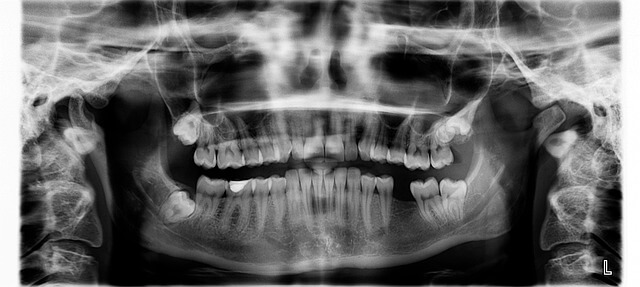

치아 신경치료 과정 첫 단계를 겪을 때, 저는 극심한 통증으로 서울 강남 치과를 찾았어요. 하단 어금니 충치가 신경까지 침투해 밤새 얼음물 마실 때도 찌르는 듯 아팠죠. 치아 신경치료 과정 시작으로 X-ray 촬영부터, 치아 신경치료 과정 정확히 확인하니 뿌리 끝에 염증 부종이 보였습니다. 치아 신경치료 과정 이 경험처럼, 대부분 1단계는 30분 마취 후 진행돼요.

치아 신경치료 과정 첫 방문은 항상 X-ray 촬영부터예요. 치아 신경치료 과정 제 경우 2024년 3월, 하단 오른쪽 6번 어금니가 밤새 쑤시는 통증으로 시작됐죠. 치과 도착 후 치아 신경치료 과정 확인하니 충치가 법랑질 넘어 상아질까지, 신경 가까이 침투했어요. 치아 신경치료 과정 마취제 2% 리도카인 1.8ml 주사 후 5분 기다리면 완전 무감각! 치아 신경치료 과정 드릴로 충치 긁어내고, 치아 꼭대기 중앙에 2.5mm 직경 구멍 내요. 이게 근관와동으로, 가는 신경관 통로 확보예요.

치아 신경치료 과정 여기서 파일이라는 가느다란 바늘 모양 도구로 신경조직 '발수' 시작해요. 치아 신경치료 과정 뿌리 끝까지 18mm 길이 측정하며 염증 조직 싹 제거, EDTA 용액으로 세척하죠. 치아 신경치료 과정 30분 만에 약물 주입 후 임시 충전재로 막아요. 치아 신경치료 과정 제가 느꼈던 건 마취 풀린 후 저림 2시간, 다음 날부터 70% 통증 줄었어요. 치아 신경치료 과정 4일 후 2단계 예약 잡고 집에 가니 얼음물 마셔도 안 아팠습니다.

치아 신경치료 과정 2단계 신경관 확대와 소독

치아 신경치료 과정 두 번째는 1주일 후, 붓기 확인부터예요. 치아 신경치료 과정 제 어금니처럼 3개 뿌리 있는 치아는 확대 작업 필수죠. 치아 신경치료 과정 파일 크기 #15에서 #40까지 점차 키워가며 0.4mm 폭으로 넓혀요. 치아 신경치료 과정 이 과정에서 과산화수소+소금물 소독제 뿌려 세균 99% 사멸! 치아 신경치료 과정 45분 동안 엔진 돌려 근관 성형, X-ray로 뿌리 끝 밀봉 확인해요.

치아 신경치료 과정 세 번째 방문, 염증 완전 사라진지 확인해요. 치아 신경치료 과정 제 경우 2주째, 비어있는 신경관에 구트라퍼차라는 고무 충전물 밀어 넣어요. 치아 신경치료 과정 가열해 부드럽게 주입 후 세정제로 다듬고, 최종 X-ray로 뿌리 1mm 안쪽까지 꽉 찬지 봐요. 치아 신경치료 과정 이게 근관 충전, 세균 재침투 막는 핵심!

- 3단계: 최종 소독 후 구트라퍼차 충전물 삽입, X-ray로 뿌리 끝 확인.